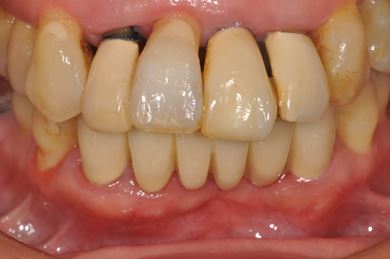

インプラントの症例写真 IMPLANT

骨再生スピードインプラント治療+セラミック治療

| 性別/年齢 | 女性 / 43歳 | ||||||||||||||||||||||||||||||||

| 主訴 | 骨が薄いが、インプラント治療を希望。 | ||||||||||||||||||||||||||||||||

| 治療内容 | インプラント9本(抜歯即日スピードインプラント、ソケットリフト、テンポラリーインプラント+仮歯)、メタルボンドセラミッククラウン18本、メタルボンドセラミックブリッジ6本(メタルボンド用土台6本)、遊離歯肉移植術 | ||||||||||||||||||||||||||||||||